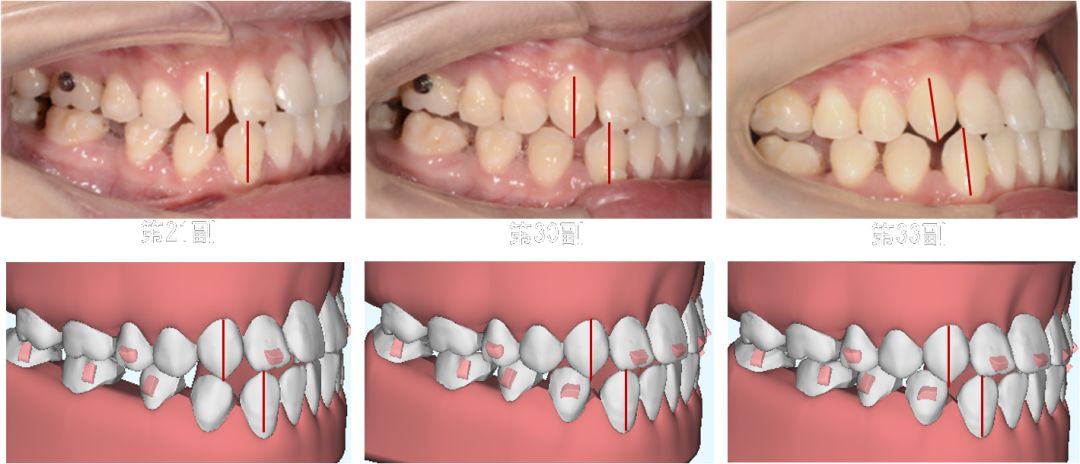

第8副,矫治器与牙面贴合,矫治过程中配合III类牵引,有利于尖牙、磨牙关系的改善。

第20副,矫治器与牙面贴合,近中矩形附件使矫治器对47牙有较好的固位,47牙与45相对移动,磨牙尖牙关系改善。

第30副矫治器时,其余牙位矫治器还是比较贴合,但是47牙近中出现了低合与矫治器间隙变大,嘱患者使用咬胶,利用矫治器的力量竖直47牙。

第33副,由于47牙持续的前倾,我们进行了矫治设计的反馈,患者由于干扰的去除,咬合支点的前移,出现了颌位的后退。因为这个原因,实现了比矫治设计更好的尖牙磨牙关系。所以这次我们反馈时提交的是cr位的咬合记录。